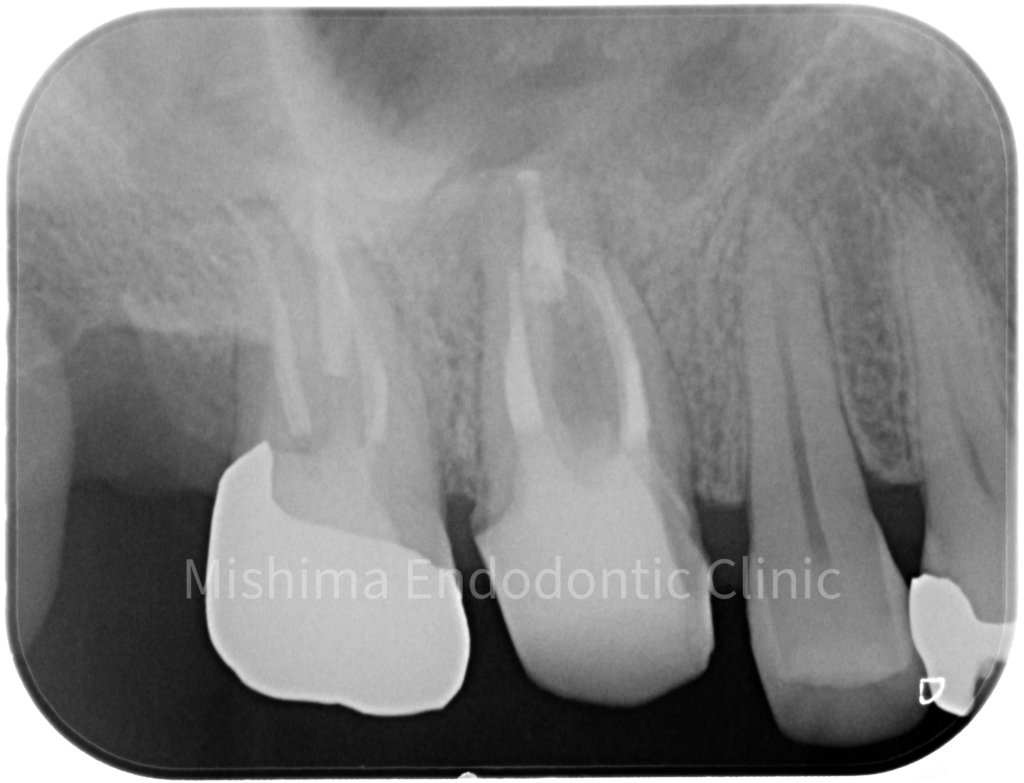

Before

| 主訴 | 急にすごく痛くなった |

| 治療内容 | 打診痛、自発痛、上顎洞粘膜の肥厚、遠心根に破折ファイルを認めた。破折ファイルは除去し、根管治療を行なった |

| 治療期間・治療回数 | 1週間 / 2回 |

| 治療費用 | 根管治療 154,000円 隔壁 5,000円 支台築造(レジンコア) 5,500円 破折ファイル除去 33,000円 (全て税込) |

術前